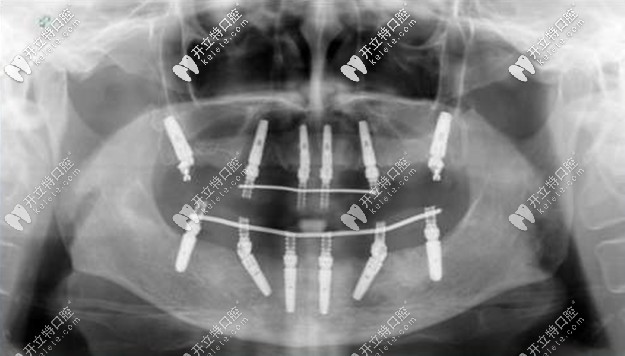

老人種牙All-on-4全口種植牙——價(jià)格在16萬(wàn)-25萬(wàn)之間,上下牙各四顆種植釘,利用8個(gè)植體就可以變好全口牙齒的咀嚼功能,種植顆數(shù)少,相比柵欄式種植更加便宜。

allon4全口種植牙